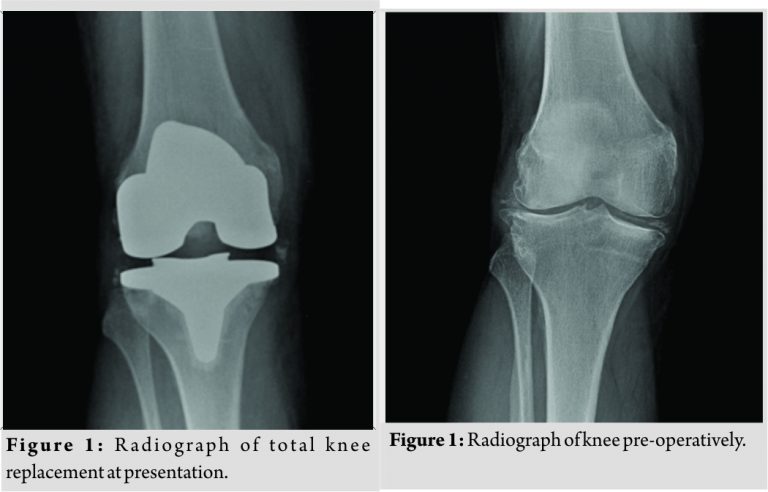

Our patient is a 77-year-oldfemale who underwent a TKR of her right knee for symptomatic osteoarthritis. She suffers from tablet controlled type 2 diabetes mellitus, glaucoma, and OA of her hips and left knee but is otherwise fit and well and has good mobility. She had no previous history of gout or pseudogout. Her right knee had been treated with four steroid injections over the course of the past3 years; however, the efficacy of these diminished and so the decision for arthroplasty was made. Our patient presented through the Emergency Department of our hospital 5 weeks following her operation complaining of a 3-day history of increasing pain, swelling, and stiffness of her right leg with difficulty to weight bear. Her knee had been improving steadily over the 4 weeks following her operation, and she did not experience any wound problems. On clinical examination, her knee was swollen, hot, and very tender to touch. She had a range of motion of 10–30° limited by pain, and she recorded a single temperature reading of 38.0 with a slight tachycardia at presentation. She had elevated inflammatory markers: C-reactive protein 98.9 mg/L and white cell count 16.2 ×109/L with neutrophils at 13.92 ×109/L. Radiographs (Fig. 1) were unremarkable with no evidence of loosening. An ultrasound scan was performed to rule out deep vein thrombosis. Her knee was aspirated under sterile conditions in the operating theater, and 60mL of cloudy straw-coloured fluid was drained. The joint was aspirated to dryness. Analysis of the aspirate revealed the presence of calcium pyrophosphate dihydrate crystals and a high level of white cells, and there were no organisms seen on Gram stain. She was put in a cricket pad splint for comfort, and nonsteroidal anti-inflammatory drugs (NSAIDs) were started, but no antibiotics were administered. She was provisionally booked for a washout the next morning. Our patient improved clinically overnight and so antibiotics or formal washout was not deemed necessary, and she was confidently diagnosed with pseudogout. Enrichment cultures of her aspirate did not grow any microorganisms. Her symptoms resolved over the next week and she has not had any further exacerbations to date.